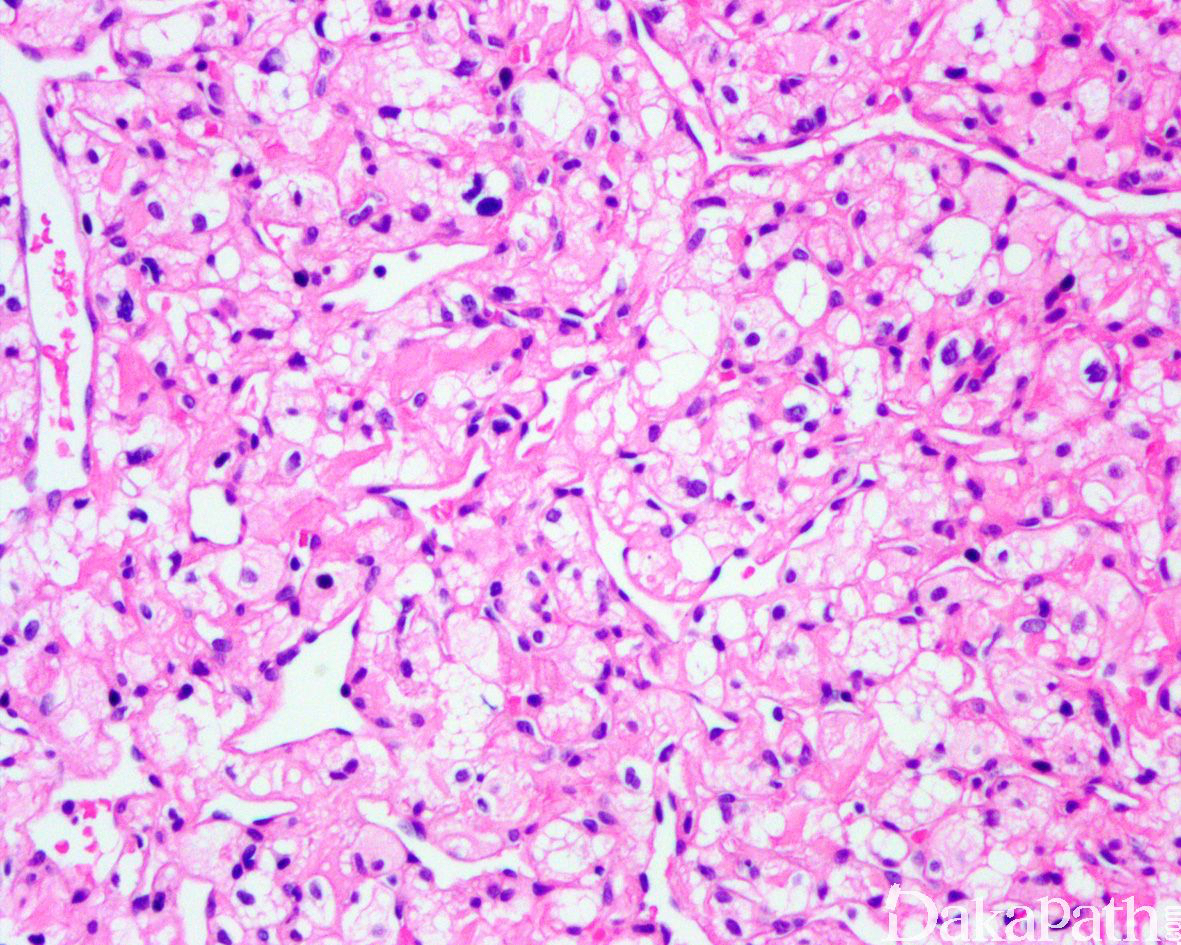

形态学类似于中枢神经毛细血管血管母细胞瘤,由间质细胞和大量毛细血管构成。

肿瘤与周围肾组织分界清楚,边缘可见内陷的肾小管,肿瘤间质血管丰富,分支血管网间可见卵圆形瘤细胞呈片状、或分叶结节状增生,局部可见瘤细胞围绕血管呈放射状排列;

细胞胞浆淡染或嗜酸性,胞浆内多泡状淡染脂质空泡,有些病例可见横纹肌样细胞形态,也可见大的嗜酸性小球和局灶的钙化;

大多数病例细胞仅轻微多形性,偶尔可见怪异细胞。